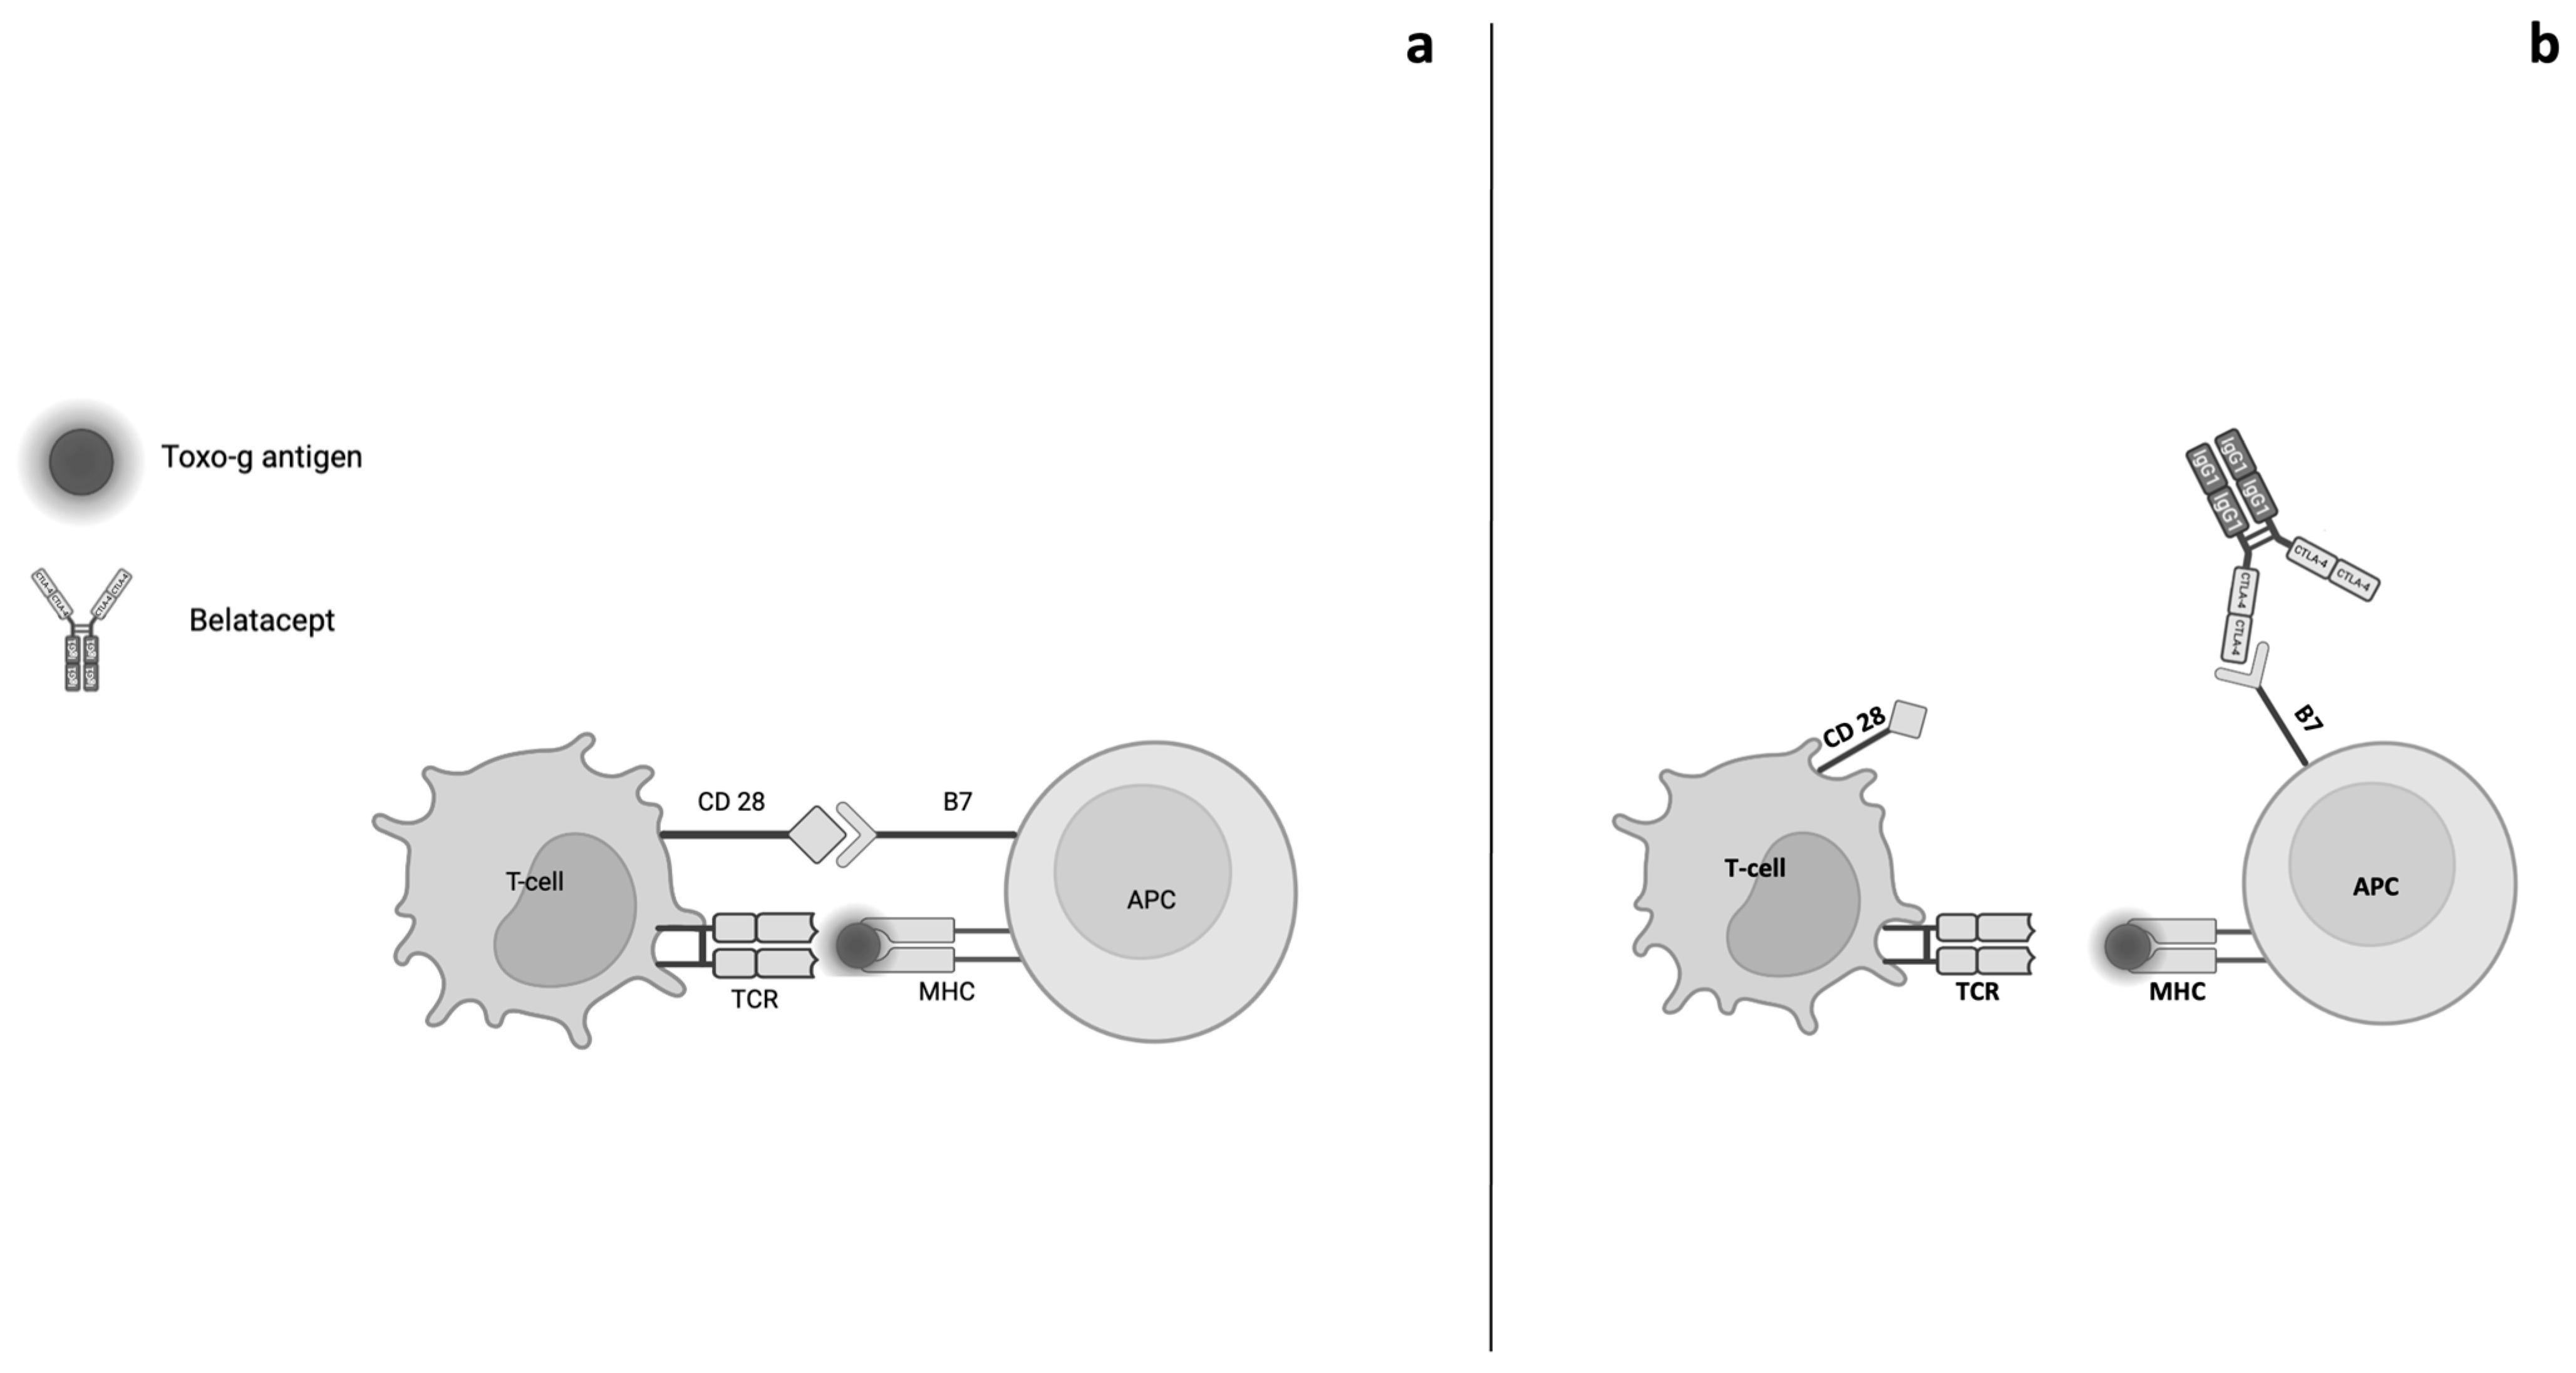

2. Belatacept Pharmacodynamics and Genetic Factors

- Walker, L.S.; Sansom, D.M. The emerging role of CTLA4 as a cell-extrinsic regulator of T cell responses. Nat. Rev. Immunol. 2011, 11, 852–863. [Google Scholar] [CrossRef]

- Gardner, D.; Jeffery, L.E.; Sansom, D.M. Understanding the CD28/CTLA-4 (CD152) pathway and its implications for costimulatory blockade. Am. J. Transplant. 2014, 14, 1985–1991. [Google Scholar] [CrossRef]